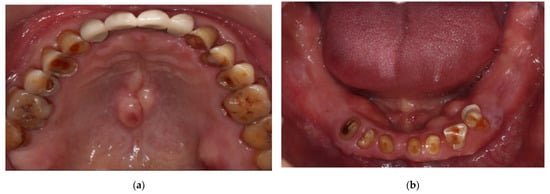

2. Case Description